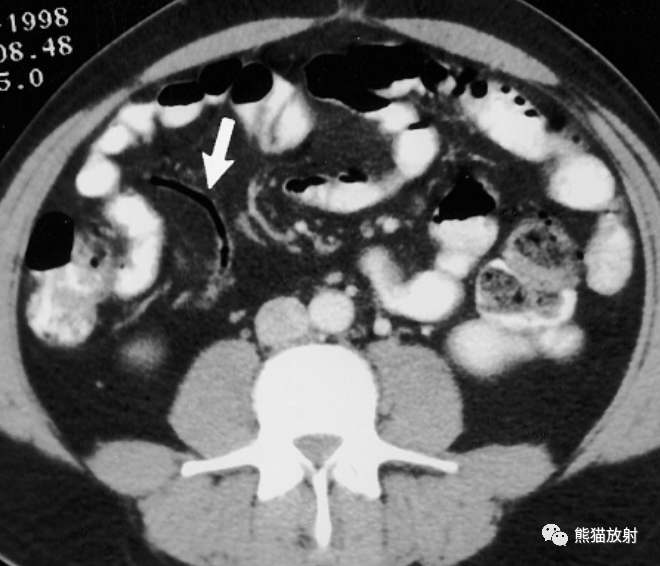

急性阑尾炎ct诊断

图片尺寸1024x750